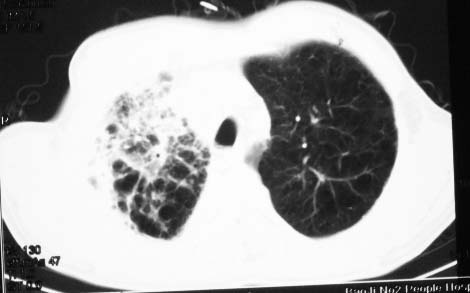

影象表现:右肺上叶大片状、网格状及索条致密影,蜂窝影,其内参杂斑点状小结节,密度不均匀,内见含气支气管像,纵隔内见肿大淋巴结.

影象表现:右肺上叶大片状、网格状及索条致密影,蜂窝影,其内参杂斑点状小结节,密度不均匀,内见枯枝样含气支气管像,纵隔内见肿大淋巴结.胸膜广泛增厚,前胸壁似受累.少量胸腔积液.纵隔内淋巴结的直径>1.5cm.右侧胸廓体积缩小.考虑:1 肺结核合并间质纤维化 2 细支气管肺泡癌

右肺上叶大片状、网格状及索条致密影,蜂窝影,其内参杂斑点状小结节,密度不均匀,内见枯枝样含气支气管像,纵隔内见肿大淋巴结.胸膜广泛增厚,前胸壁受累增厚.少量胸腔积液.纵隔内淋巴结的直径>1.5cm.右侧胸廓体积缩小.考虑: 细支气管肺泡癌并肺内癌性淋巴管炎。